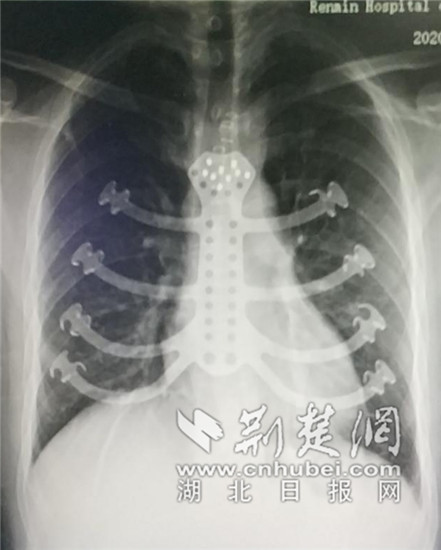

专家助其重建了一个“钢筋铁骨”的新胸廓 。(通讯员供图)

荆楚网客户端一荆楚网消息(采访人员林琳 通讯员邹亚琴)37岁的李先生不幸被胸部肿瘤“盯”上 , 然而 , 切除肿瘤的同时 , 他也将失去胸骨和邻近肋软骨 , 造成前胸部位的缺损 。近日 , 武汉大学人民医院东院胸外科专家团队成功为他切除肿瘤的同时 , 植入“私人订制”的3D打印钛合金胸骨肋骨复合体 , 助他重建了一个“钢筋铁骨”的新胸廓 。

历时一周 , 以李先生CT等影像资料为模板 , 完美贴合肋骨及胸骨柄的3D胸骨模型制作完成 。医生和工程师们反复商讨和修改 , 最终制作出1∶1钛合金材质的“钢筋铁骨” 。3D打印的钛合金强度远大于人体骨骼 , 重量也偏轻 , 不会造成患者胸部压迫等不适 , 且钛合金材料人体排异性概率较低 , 能有效减少术后心肺并发症的发生 。

8月26日 , 在黄杰教授的指导下 , 在麻醉医师的保驾护航下 , 谢颂平副教授团队为李先生成功实施了胸骨肿瘤切除及3D打印钛合金胸廓重建手术 。术后一周 , 李先生就拔除了全部的引流管 。9月7日 , 李先生顺利康复出院 。

【|罹患肿瘤后肋骨切除 专家助其重建“钢筋铁骨”新胸廓】谢颂平副教授介绍 , 胸骨肿瘤是一种较为少见的疾病 , 约占全身骨肿瘤的7%~8% , 多数为恶性 , 手术切除是治疗的首选方法 , 但肿瘤切除后需合理地修复缺损 , 进行胸廓重建 。3D打印技术很好地解决了材料问题 , 并且能够做到与人体无缝吻合 。